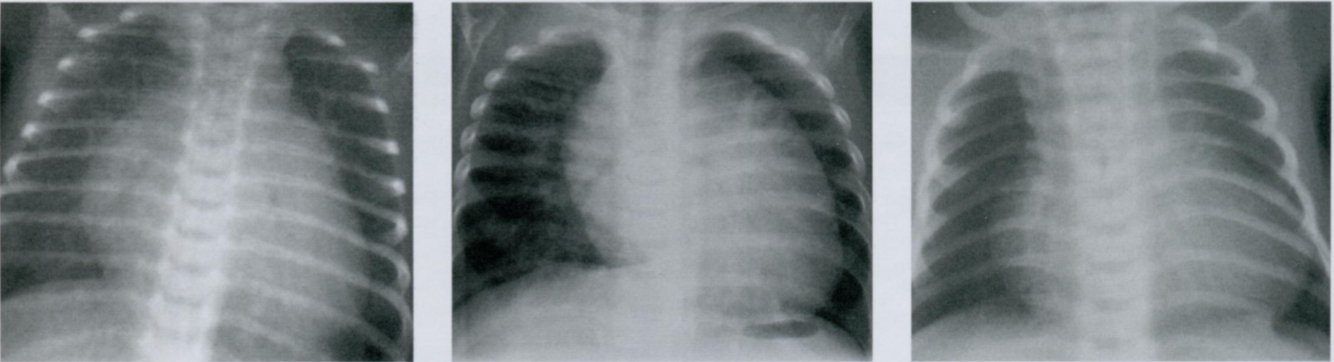

Основная задача рентгенологического исследования при врожденных пороках сердца - различить пороки, сопровождающиеся увеличением и уменьшением кровотока в малом круге кровообращения. Расширение тени сердца является неспецифическим симптомом и зависит от степени тяжести порока.

Дефект межжелудочковой перегородки (ДМЖП, первый снимок) и открытый артериальный проток (второй снимок)

являются характерными врожденными пороками с лево-правым сбросом крови и увеличением перфузии легких.

В противоположность этому, такие пороки, как атрезия легочного ствола (третий снимок) и тетрада Фалло характеризуются уменьшением легочного кровотока, что вызывает обеднение легочного рисунка (повышение прозрачности легочных полей) на рентгенограммах грудной клетки.